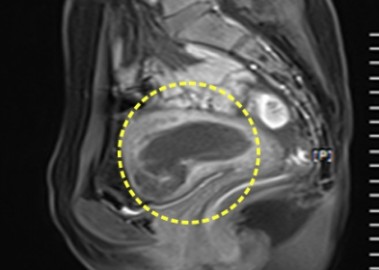

거대 자궁선근증 치료 사례